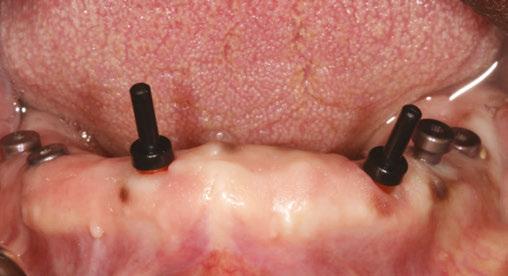

Figure

the prosthetic restorative space due to the height of additional components needed to compensate. For instance, in a recent case involving a mandibular overdenture, the use of Locator Angled abutments allowed seamless adaptation to significant divergence between anterior and posterior implants. The result was a prosthesis with superior retention, stability, and patient satisfaction without compromising the gingival esthetics or the longevity of the attachment system. Moreover, the Locator Angled system simplifies chairside adjustments, reducing the need for extensive prosthetic modifications or complex restorative solutions that could increase treatment time and cost. By

providing a predictable seating path and robust retention, these abutments ensure a streamlined workflow and fewer prosthetic and post-delivery complications. For the patient, this translates to improved comfort and confidence in their removable prosthetic solution.

Figure 2: Locator Angled abutment placed using a hex driver

Figure 3: Angled Locator abutment in place

Figure 4: Standard Locator abutments (upper left) presented with increased angulation (top right). Locator Angled abutments placed (bottom left) resulting in more parallelism (bottom right)

Figure 5: Completed Locator FIXED case with Locator Angled abutments